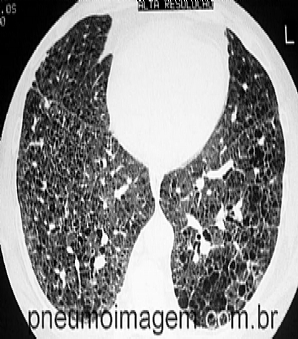

Veja imagens de Fibrose Pulmonar Idiopátca no PneumoImagem,

clicando aqui.